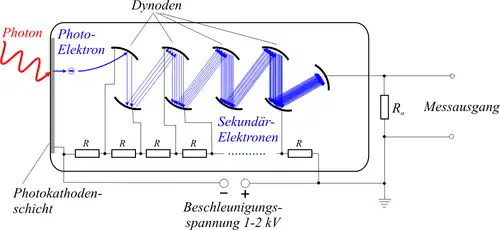

In den klinischen PET-Systemen bis in die 2020er Jahre wurden für den Nachweis der Szintillationen Photomultiplier verwendet, da es damals die empfindlichsten Nachweisinstrumente für die sehr schwachen Lichtblitze waren. Heute, Mitte der 2020er Jahre, gibt es sowohl niederpreisige analoge Systeme, wie auch höherpreisige digitale Systeme. Ein Beispiel für ein im Jahr 2024 mit analogen Photomultipliern arbeitendes Gerät ist bei GE der Discovery IQ, digital akquiriert der Omni Legend. Bei Siemens ist der Biograph Horizon mit Photomultipliern ausgestattet, der Biograph Trinion arbeitet digital. United Imaging hat nur noch digitale Systeme. Das Vereos System von Philips arbeitet digital.[7]

Photomultiplier

Die Szintillationskristalle werden entweder eingesägt, oder mehrere Kristalle werden miteinander verklebt. An den Kristallgrenzen kommt es zur Reflexion der Photonen, die so in Richtung der Detektoren gelenkt werden. Dies ermöglicht eine genauere Lokalisation als in einem homogenen, einzelnen Kristallblock. Mehrere Photomultiplier „blickten“ zusammen auf eine Gruppe von Szintillationskristallen und waren entweder direkt oder über Lichtleiter mit dem Szintillationskristall verbunden. Die Lokalisation der Szintillationen erfolgt nach dem Prinzip der Anger-Kamera durch Wichtung der Helligkeit der in den Photomultipliern registrierten Szintillationen.